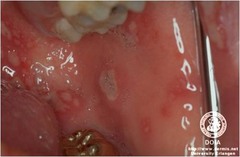

-moderately painful swelling and ulceration, acute onset -most common at the junction of the hard and soft palate -necrosis of salivary gland -cause:compromised blood supply